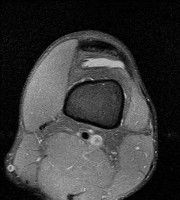

안녕하세요 8년전 십자인대 수술하고 최근 무리한 운동에 무릎 불편감이 생겨서

mri 찍었습니다.

진단결과는 첫 찍은 병원에서 활액막염 이라는 진단을 받았습니다. 혹시 봐주실 수 있으실까요?

올라온 MRI가 단편적이라서 정확한 진단에 어려움이 있지만 십자인대에는 큰 이상이 있지는 않은것 같으며, 무릎관절내 물이 있는 것으로 보아 활액막염의 진단이 맞을 것 같습니다.

하지만 단편적인 영상이기 때문에 촬영병원에서 정확한 판독지 등을 받으시는 것이 좋겠습니다.